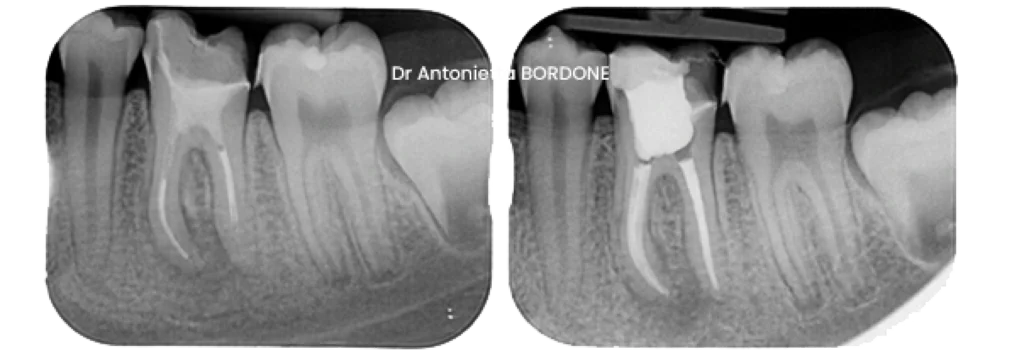

Exemple de retraitement canalaire d’une molaire inférieure :

Pourquoi un provisoire et un contrôle différé ?

La guérison osseuse nécessite du temps. En effet, une lésion d’origine endodontique ne disparaît pas en quelques jours. Le provisoire sert donc de phase test. Il maintient l’étanchéité pendant la cicatrisation. Ensuite, un contrôle clinique vérifie l’absence de symptômes. Une radiographie confirme l’amélioration de la lésion. Quand tout évolue favorablement, la restauration définitive peut être posée. Ce temps réfléchi sécurise le résultat et limite les récidives.